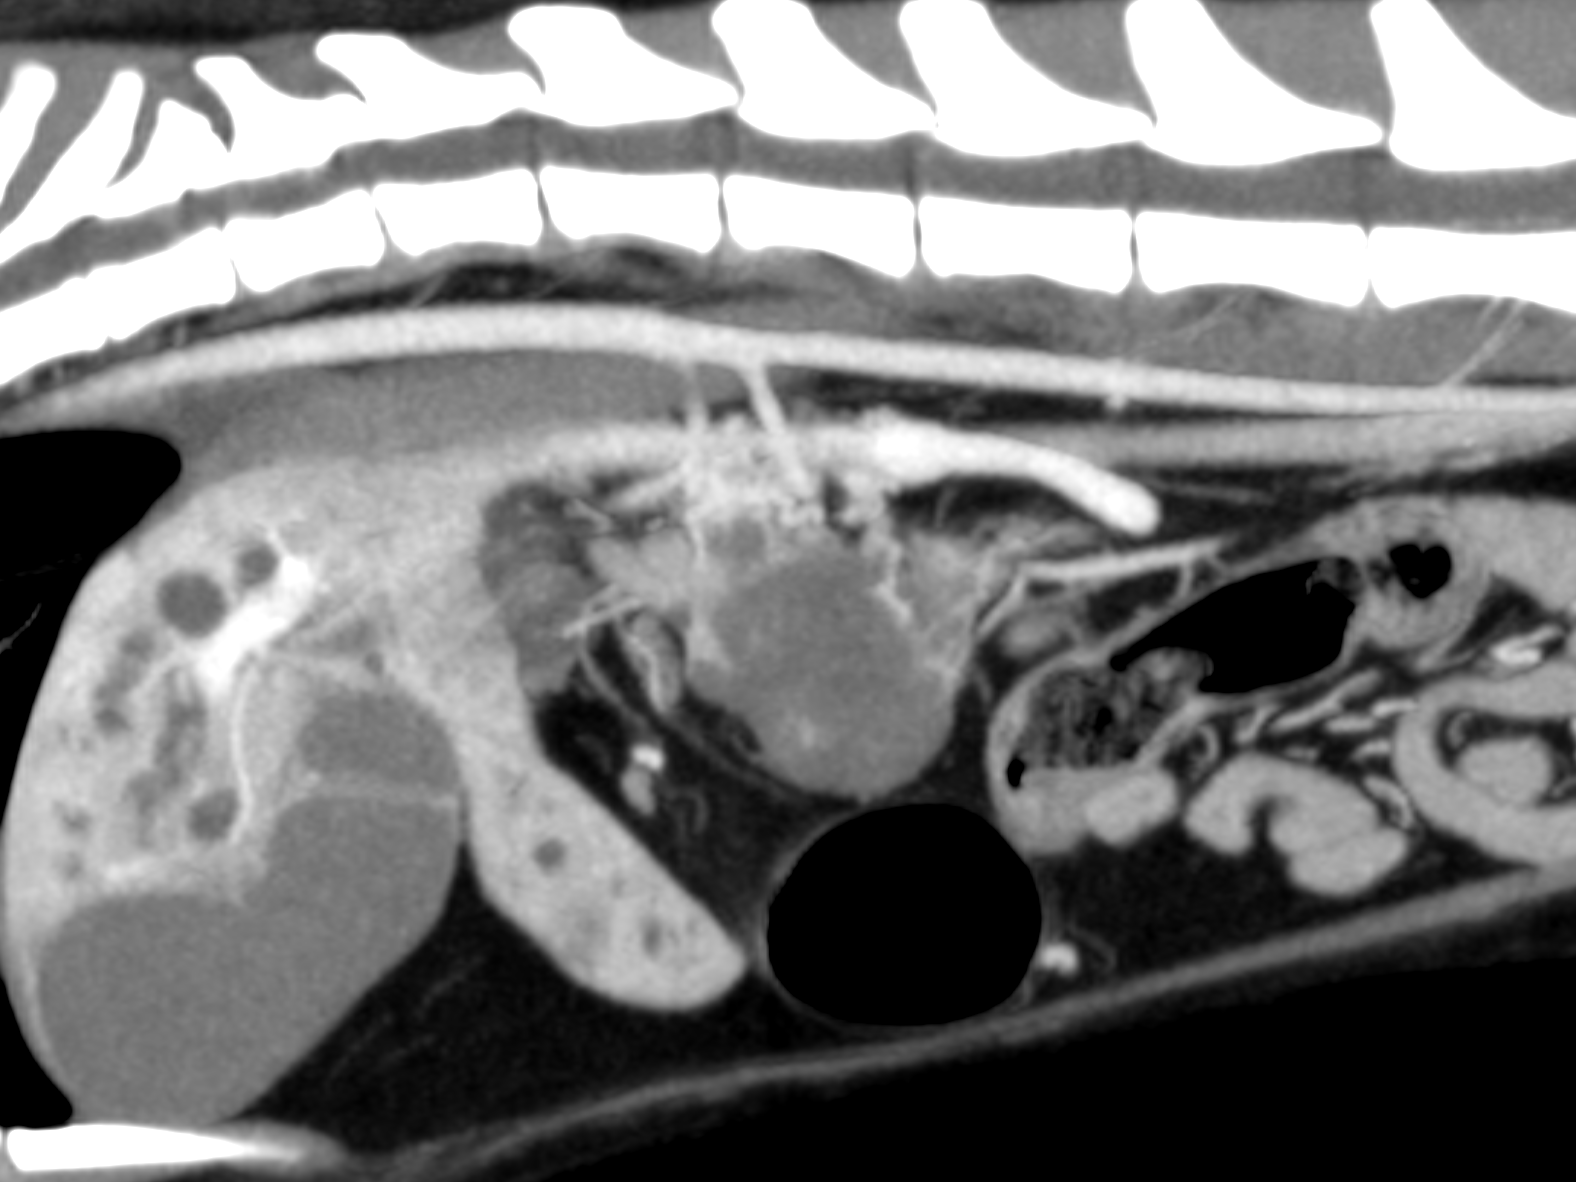

膵臓腫瘍による肝外胆管閉塞

腹部エコー検査で総胆管開口部に腫瘤が形成されており、これにより胆汁が腸へ流れない状態となっていました。

これに対する治療として、生検を兼ねた胆嚢十二指腸吻合術をおこないました。

病理検査の結果は膵臓癌であり予後は厳しいですが、術後は黄疸も改善し、少しではありますが自分から食べることができています。